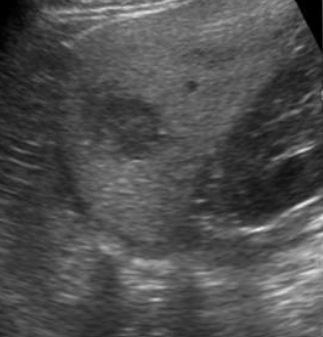

Abdominal Aortic Aneurysm (AAA) Screening: Guidelines, Risks, and Follow-Up

Learn who should be screened for abdominal aortic aneurysm (AAA), major risk factors, guideline differences, and how to monitor detected aneurysms.

Read time: 5-6 minutes